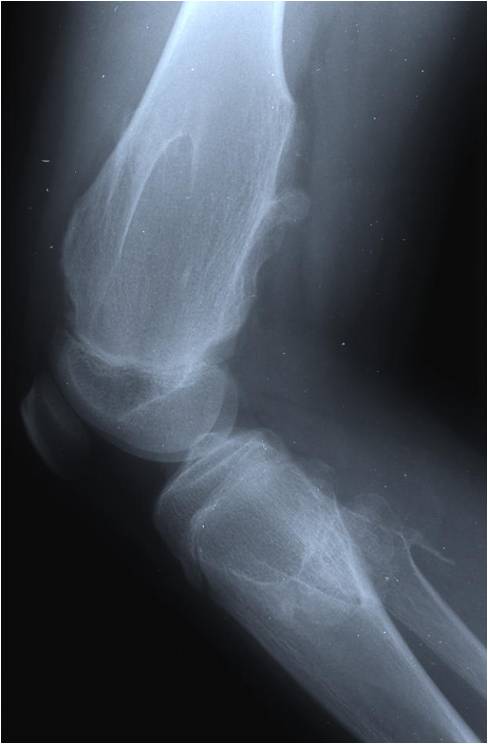

Radiographic Presentation

Plain X-rays:

- Projects from bone with narrow (pedunculated) to broad (sessile) stalk

- Corticomedullary continuity: Medullary bone continuous with that of osteochondroma and cortex blends with that of osteochondroma

- Calcification in cartilaginous cap (“Ring and Arc” and stippled calcifications)

- Lobular growth pattern

- Long bones: arise from metaphysis, grows away from epiphysis toward diaphysis,

- May be associated with failure of tubulation in Multiple Hereditary Exostosis

- Flat bones: tend to be larger and sessile, variable appearance

- Cartilage cap thickness is visualized best on MRI, not XR